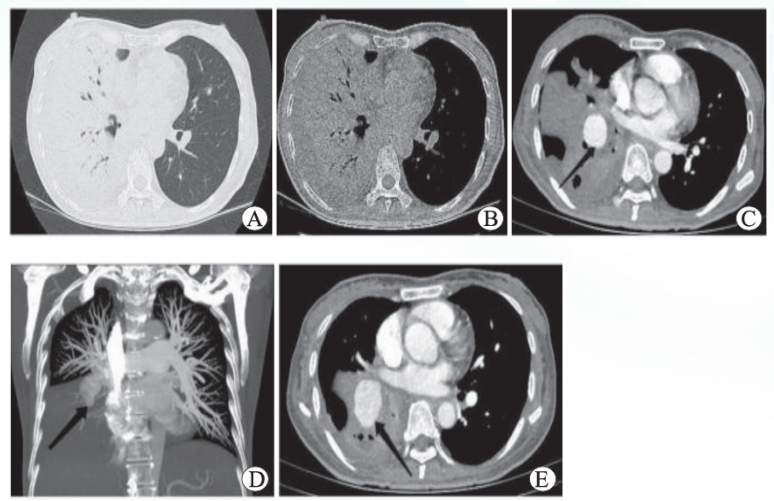

肺动脉瘤包括真性和假性动脉瘤, 其中感染是假性动脉瘤的常见病因从相关文献检索结果来看, 感染因素中以结核和梅毒较为多见。此外, 感染性心内膜炎、肺脓肿以及葡萄球菌、念珠菌、毛霉曲霉等引起的感染也有报道(图15)

毛霉引起的假性动脉瘤给人印象较深。2021年Asian Cardiovasc Thorac Ann杂志报道了一例45岁糖尿病患者肺毛霉病引起的肺假性动脉瘤(图16)在体外循环支持下进行了紧急右全肺切除术。肺标本组织病理学报告证实了毛霉病。术后患者接受了两性霉素B治疗,但最终仍未能存活。真菌性肺动脉瘤预示着免疫功能低下患者的发病率和死亡率非常高。另外一篇文献是笔者科室2022年发表的文章,一例56岁糖尿病患者因肺毛霉病引发肺动脉假性动脉瘤(图17,图18),最终因大咯血死亡

16  文献报道的肺毛霉病引起的肺假性动脉瘤影像学

图源:Asian Cardiovasc Thorac Ann, 2021, 29(8):848-851.

图片

17  笔者团队报道的肺毛霉病患者胸部CT及肺动脉造影

2015年Tokai J Exp Clin Med 杂志发表的文献报道了一例65岁鼻咽癌患者因肺脓肿引起肺假性动脉瘤(图19),经手术治疗后康复。

19  文献报道肺脓肿引起的肺假性动脉瘤患者的胸部CT和三维重建

图源:Tokai J Exp Clin Med, 2015, 40(3):86-89.

本文所述病例多次检出星座链球菌文献曾报道一例因大咯血行肺切除术的患者, 术后病理及培养结果均提示为星座链球菌(图20)。但结合本文所述病例多次NGS检测结果,除星座链球菌外还存在大量其他口咽菌,而培养未发现其他细菌,考虑可能因口咽菌多为厌氧菌,难以培养,故更倾向于混合感染的判断。

20  文献报道星座链球菌引起的肺假性动脉瘤患者增强CT和切除肺的病理

图源:Int J Infect Dis, 2013, 17(11):e1064-6.